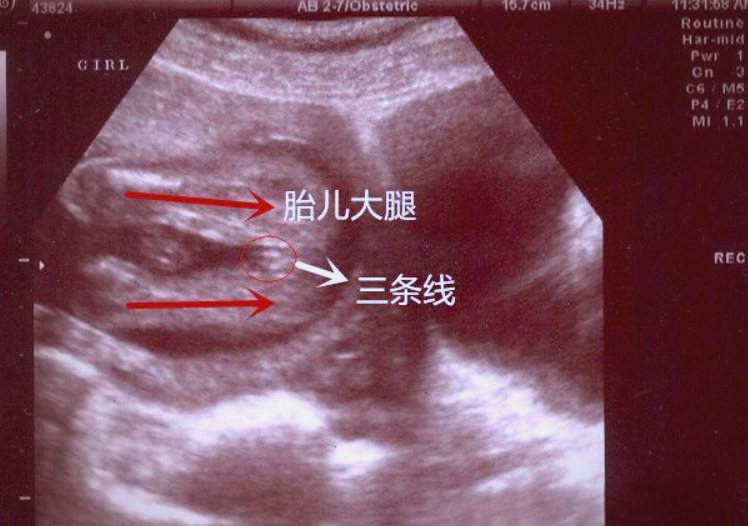

快速辨别是男宝还是女宝

胎儿的性别分化已经相当明显,对于男胎来说,其生殖器官即阴茎,在彩超